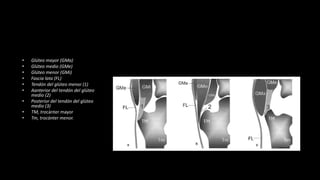

• Glúteo mayor (GMa)

• Glúteo medio (GMe)

• Glúteo menor (GMi)

• Fascia lata (FL)

• Tendón del glúteo menor (1)

• Aanterior del tendón del glúteo

medio (2)

• Posterior del tendón del glúteo

medio (3)

• TM, trocánter mayor

• Tm, trocánter menor.

• Glúteo mayor(GMa) • Glúteo medio (GMe) • Glúteo menor (GMi) • Fascia lata (FL) • Tendón del glúteo menor (1) • Aanterior del tendón del glúteo medio (2) • Posterior del tendón del glúteo medio (3) • TM, trocánter mayor • Tm, trocánter menor.